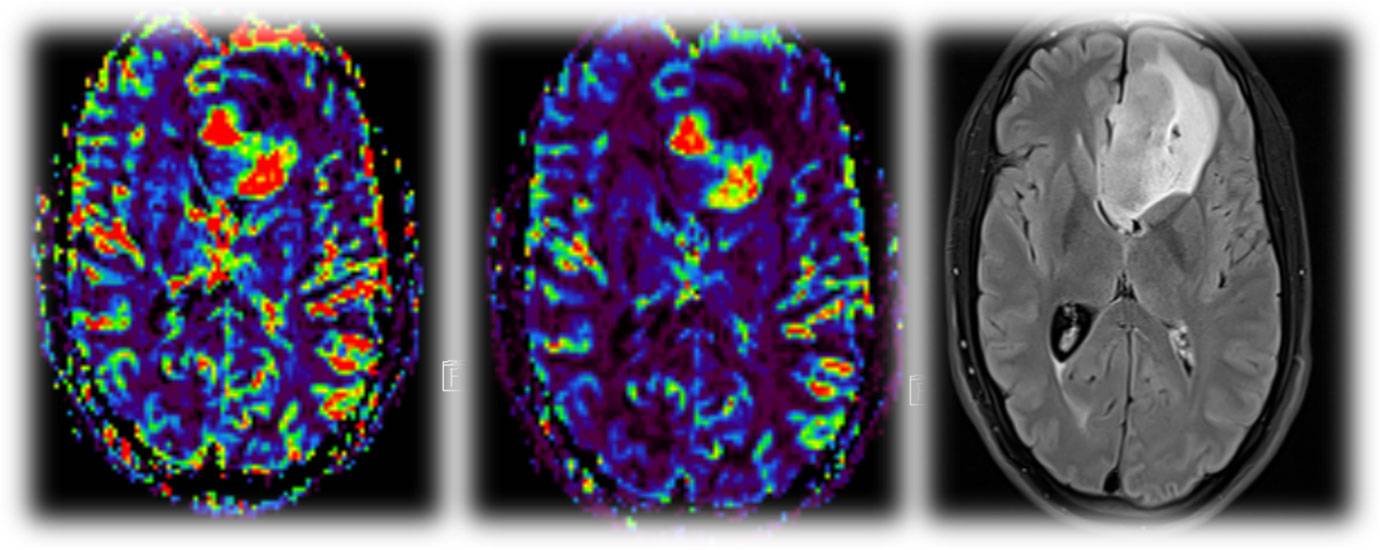

A 5-year-old male child presented with complaints of recurrent generalized tonic–clonic seizures and right-sided weakness ,predominantly involving the lower limb along with anger outbursts and abnormal behaviour.